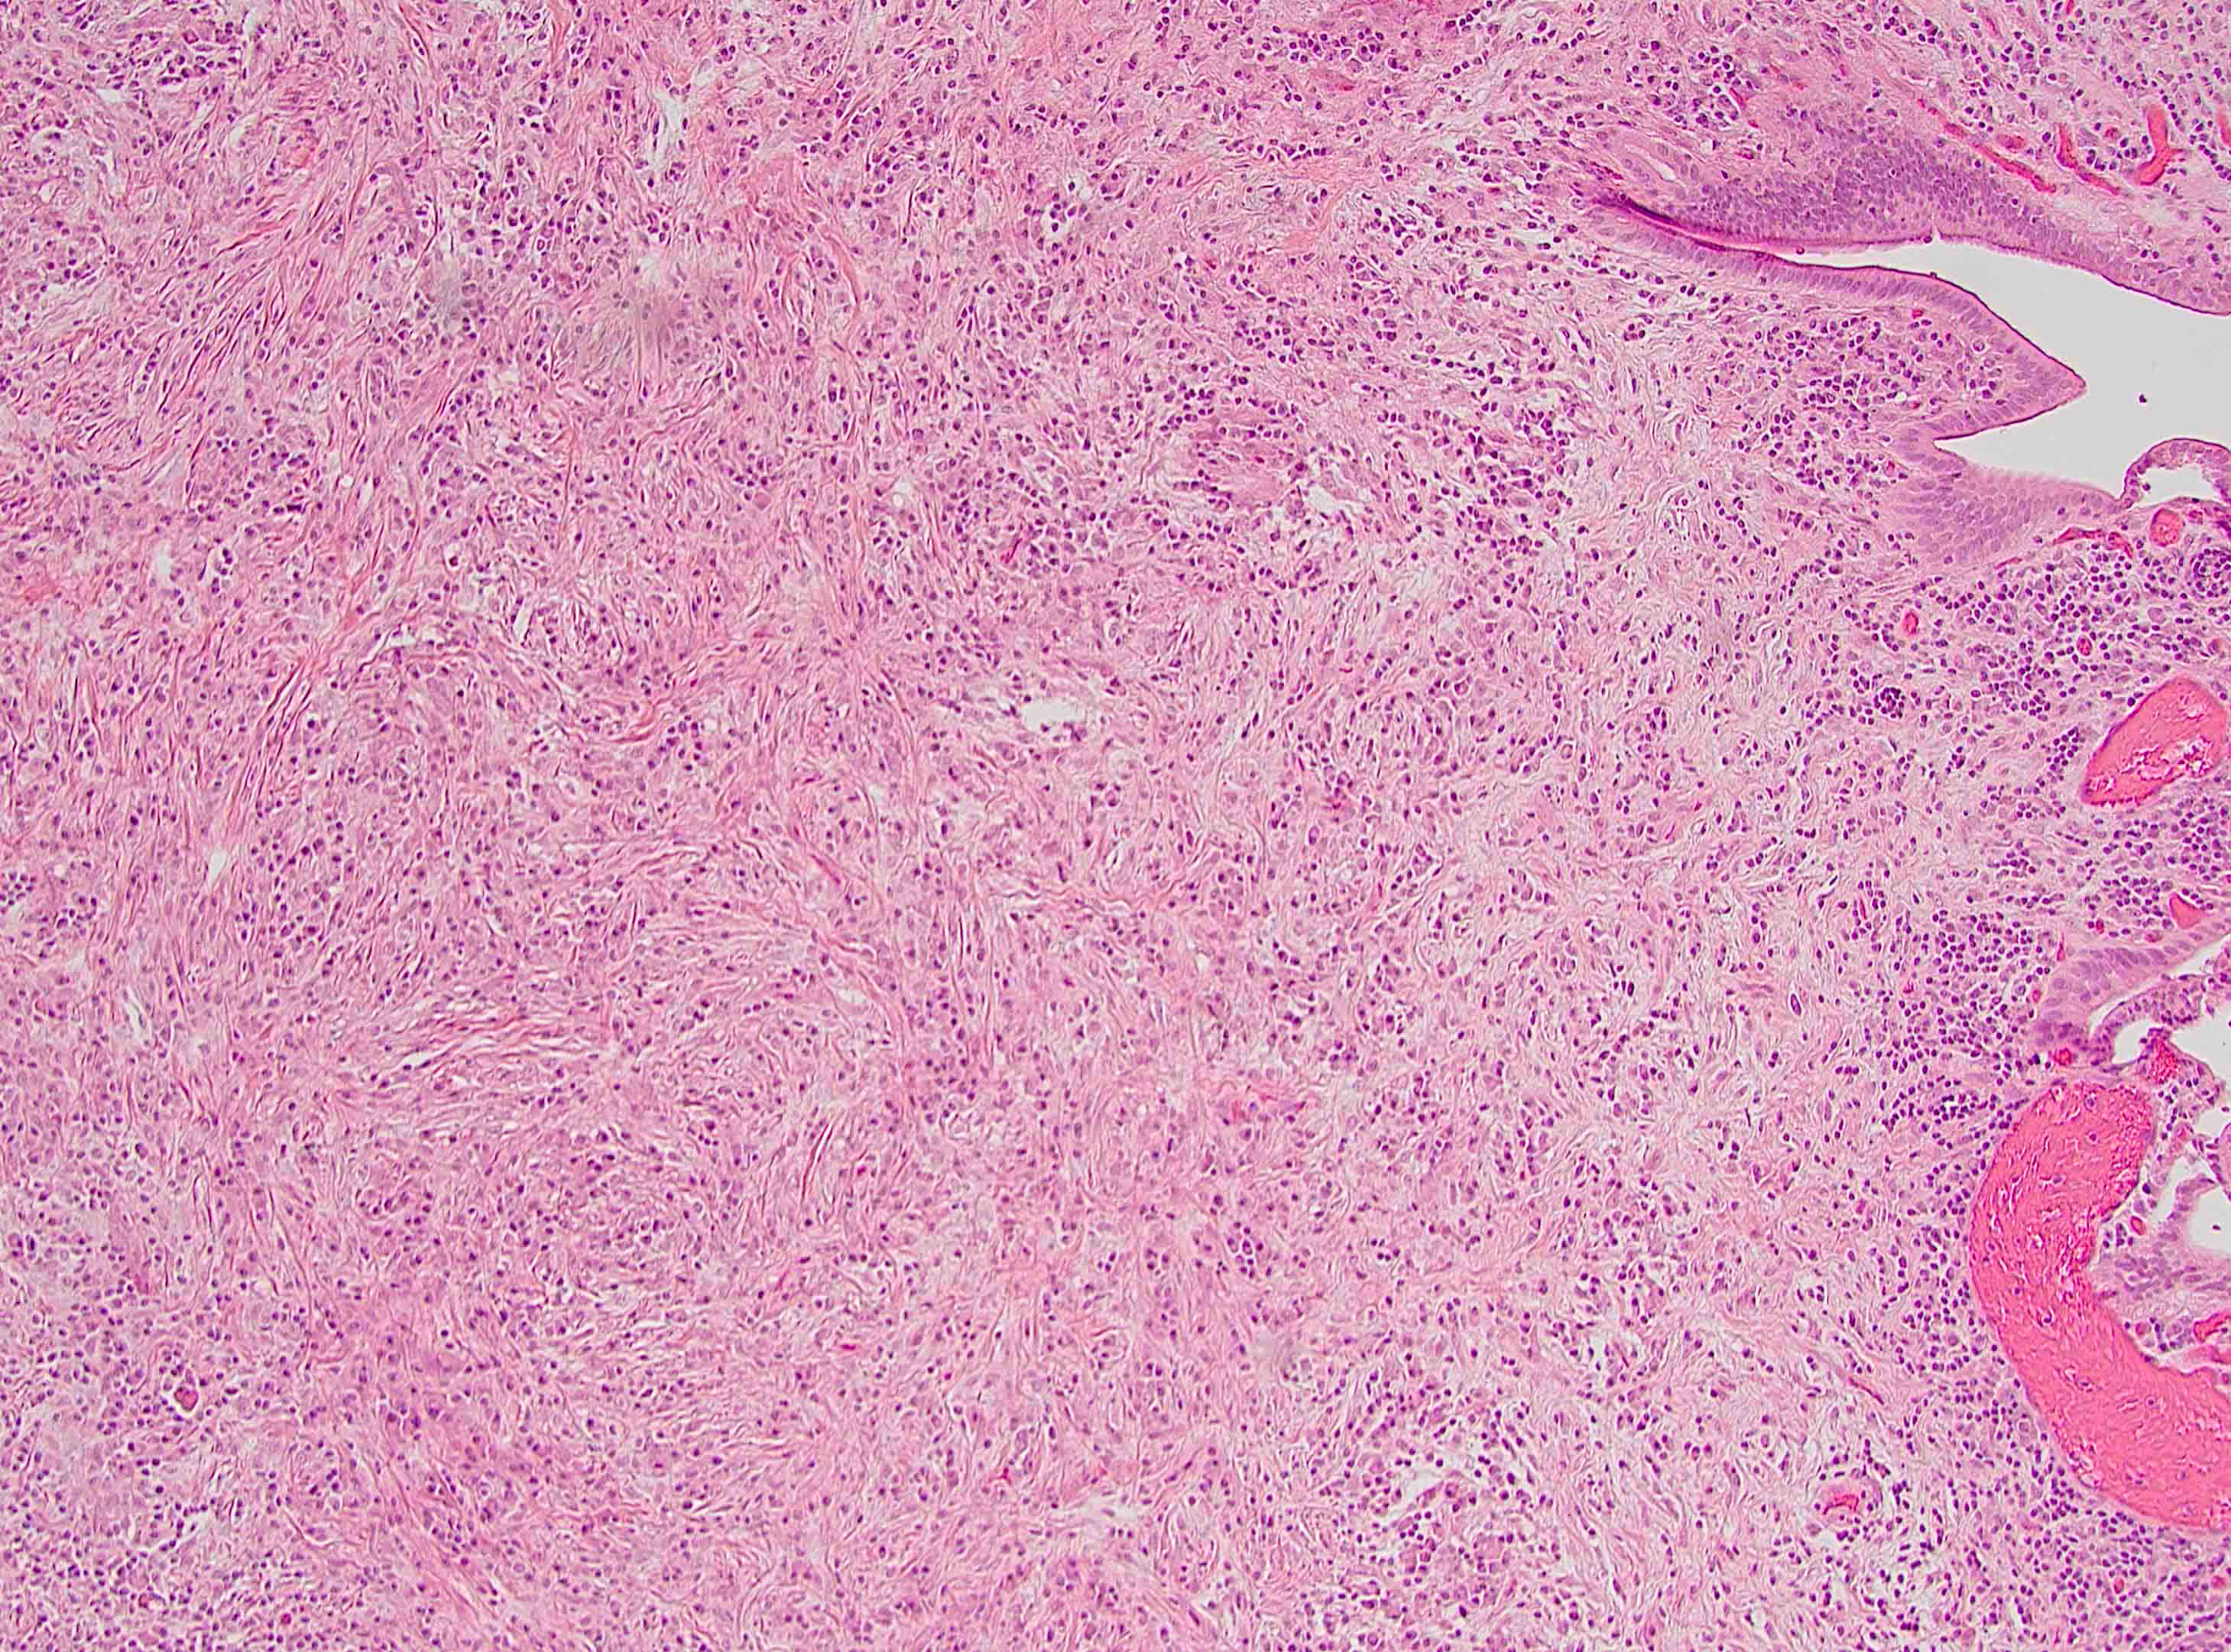

Microscopic (histologic) description

- Characteristic findings (at least 3 for level 1 criteria) (Pancreas 2011;40:352)

- Periductal lymphoplasmacytic infiltrate without granulocytic infiltration

- Obliterative phlebitis

- Storiform fibrosis

- Abundant (> 10 cells/high power field) IgG4 positive plasma cells

- Biopsy showing some but not all of the above features can be used as supportive evidence for the diagnosis of autoimmune pancreatitis (Pancreas 2011;40:352)

- Inflammation is localized within the pancreatic parenchyma and is centered around / within medium to large interlobular ducts, which causes shrinkage of the ductal lumen (Pathologica 2020;112:197)

- Inflammation can also be seen between the pancreatic parenchyma and peripancreatic adipose tissue (Pathologica 2020;112:197)

- Inflammation of the venous wall can progress to obliterative phlebitis with fibrosis of the lumen (Pathologica 2020;112:197)

- As the inflammation progresses, fibrosis becomes more diffuse, assuming a whorled or storiform pattern (Pathologica 2020;112:197)

- Perineural inflammation can also be present (Pathologica 2020;112:197)

Microscopic (histologic) images